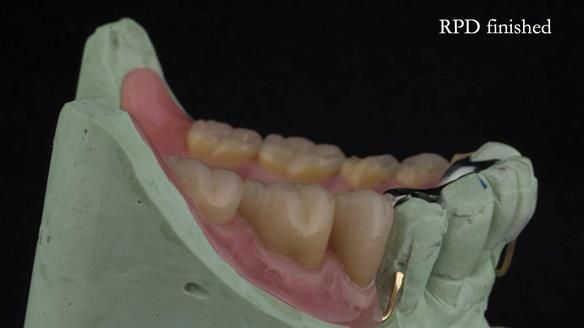

Instead, we made a Scandinavian-style, metal-based lower RPD.

It was made promptly, then relined gradually over the following year

to optimise fit, comfort, and support.

It’s worth saying that the lower denture in this case was made in the early days of Rowan and me using the Scandinavian approach. Rowan cast the metalwork himself for this denture.

Looking back, we would make this denture more hygienic now. The design and finish would be more refined and delicate, particularly when compared with the upper metalwork, which was made later using Chris Hesketh’s chrome work. I will discuss this in detail at the study club.

That said, the lower denture worked beautifully. It did exactly what it was meant to do, even though, by today’s standards, it looks a little agricultural.